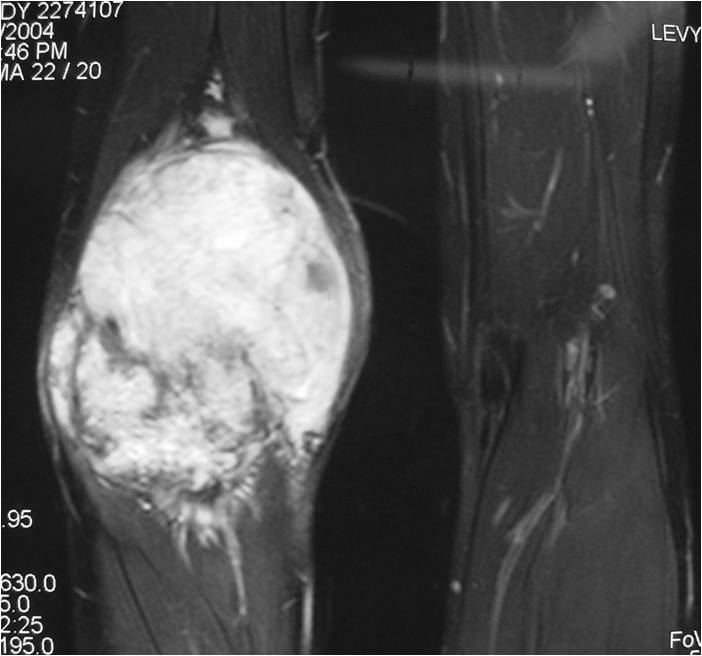

- Aggressive motheaten to permeative lesion

- Indistinct border in most cases

- Osseous destruction with a soft tissue component

- Chondroid matrix calcification may be present (60-70% of cases)

- Soft tissue mass

(Right Arrow) Cartilaginous Component